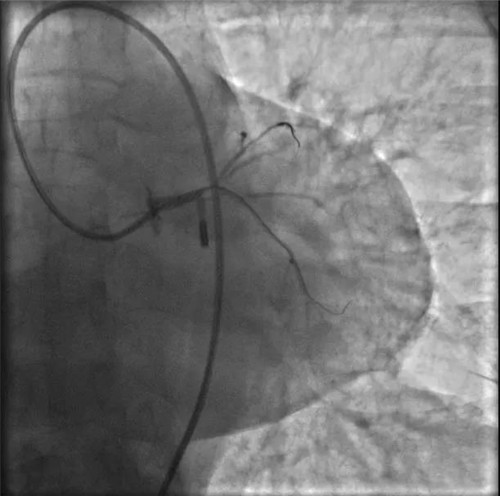

根據(jù)IVUS檢查結(jié)果,在前降支近中段至左主干植入3枚支架,充分?jǐn)U張后,狹窄完全解除,血流恢復(fù)通暢。

植入3枚支架,血流恢復(fù)通暢